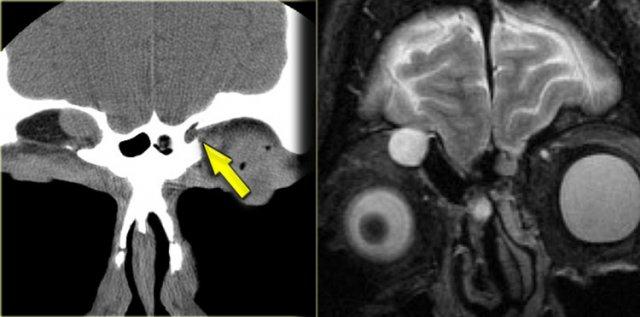

Hình ảnh bên trái của một bệnh nhân được nghi ngờ mắc u sụn ác tính (chondrosarcoma).

Trên chuỗi xung T2W, có một tổn thương giảm tín hiệu (mũi tên vàng) kèm thành phần dạng nang (mũi tên đỏ).

Trên chuỗi xung T1W trước và sau tiêm thuốc tương phản từ, khối u ngấm thuốc đồng nhất với vùng ngoại vi của thành phần nang ngấm thuốc theo chu vi.

Câu hỏi: bước tiếp theo cần thực hiện là gì?

Bước tiếp theo: chụp CT!

Trên CT, đây là hình ảnh loạn sản xơ (FD) điển hình với vỏ xương còn nguyên vẹn và hình ảnh kính mờ (ground-glass).

Nhiều tổn thương loạn sản xơ ở vùng clivus, nền sọ hoặc hốc xoang-mũi, đặc biệt ở trẻ em, có thể có thành phần nang lớn, vì vậy đừng để điều đó làm bạn phân vân trong chẩn đoán!